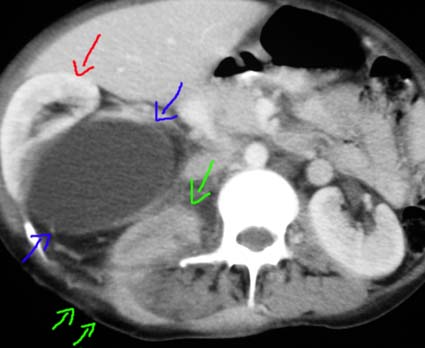

numerosos leucocitos, sin otros hallazgos específicos. Una tomografía

revela que el riñón derecho está desplazado y comprimido

por una lesión quística homogénea, bien definida,

que está en contacto con la pelvis renal. Adyacente hay una masa

retroperitoneal mal definida que está en contacto con el psoas

y que conecta con el trayecto fistuloso (Figura 1). El riñón

izquierdo aparece normal.

Figura 1.

TC, el riñón (flecha roja) está desplazado por una

lesión quística cercana al hilio (flechas azules). Se evidencia,

además, una masa retroperitoneal que llega hasta región

lumbar donde hay fístula cutánea (flechas verdes).